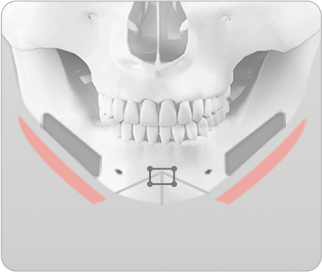

브라운의 ㅅ절골술 이용한 앞턱 수술

ㅅ절골술은 턱끝의 길이를 조절하여 길게 하거나 짧게 줄일 수 있으며, 무턱이나 주걱턱을 보형물이나 뼈 이식 없이 효과적으로 개선할 수 있습니다. 또한 동시에 비대칭이 심하거나 넓은 턱끝도 부드러운 V라인 턱끝을 만들 수 있으며, 턱끝 신경과 치아뿌리를 피해 절골하기 때문에 신경과 치아 손상없이 안전하게 수술할 수 있습니다.

ㅅ절골술 진행 시 턱끝 중앙뼈를 2~10mm 까지 다양하게 절제하여 턱끝의 넓이를 조절할 수 있습니다.